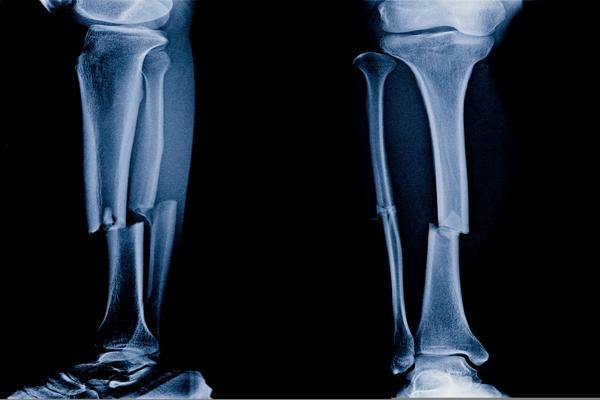

Um estudo publicado no JB&JS investigou se bifosfonatos estão associados a ausência de consolidação de fraturas.